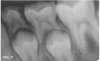

Case 1. A 9-year-old girl had a distal caries lesion of the primary canine tooth and mesial caries of the approximating primary first molar (Figure 1). With no local anesthesia and no discomfort reported by the child, a high-speed diamond bur was used to trim open the contact, exposing the lesions (Figure 2). After the site was air-dried, a flexible interdental pick was used to apply the SDF solution (Figure 3), which was blotted dry with a cotton swab after 60 seconds (Figure 4).

Fig 8. 10-year-old patient with distal caries lesion of primary  rst molar. (

Fig 8